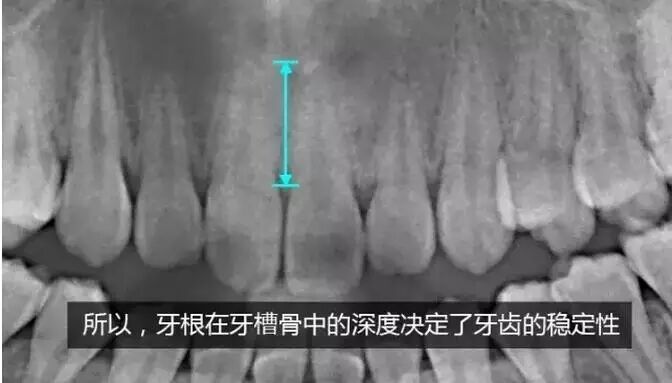

牙齿移动是一个生理性改建的过程,有点类似我们身体中的新陈代谢,是一个十分缓慢的过程。让我们来看看牙齿在矫正过程中,都在进行哪些变化:

我们可以看到,当牙齿进行移动后,牙根在骨中的长度并没有变短,所以,依旧像矫正前一样稳固。

因此我们得出一条结论:进行正规的牙齿矫正,利用的是牙齿自身可以在牙槽骨中移动这一特点,用轻柔的力量帮助牙齿移动,并且移动后的牙齿在牙槽骨中的长度没有改变,所以其稳固性也不会发生变化。